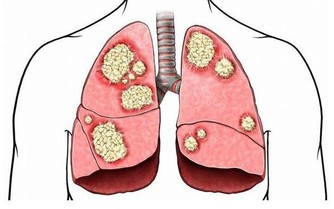

膽固醇高的危害

膽固醇的正常值是0-5.2mmo/L(0-200mg/dl),超過這個值就是表現為膽固醇高,膽固醇高的危害主要有:

1、會加快前列腺癌的生長速度,會引發腎衰竭脂類的腎臟疾病。

2、會減少人的壽命,尤其是男性的壽命同時和血管有關的中風機率會隨著增加。

3、會阻塞心臟動脈和使其變窄,更容易引發心髒病。

4、會使骨質疏鬆症的可能性變高,同時過多攝入膽固醇可導致牙周病、牙和牙隙之間的溝隙會擴大。